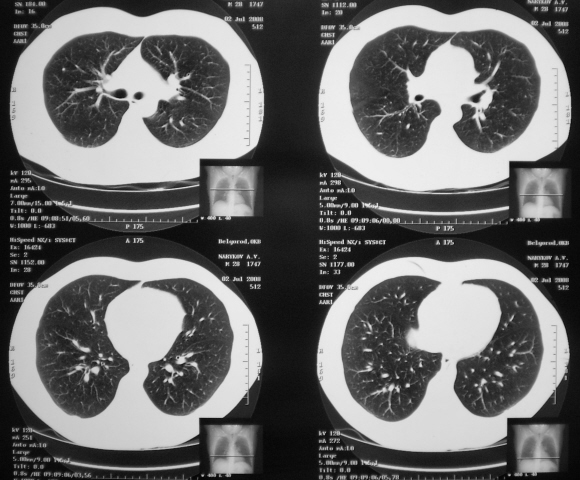

Молодой человек уже в четвертый раз поступает к нам "почти без жалоб" по поводу "спонтанного пневмоторакса". Вот, и в этот раз, после работы " с дрелью" почувствовал, что что-то "кольнуло". "Предыдущий пневмоторакс" наступил по время рвоты. А перед этим - после прыжка с табурета. Какие мнения будут уважаемые коллеги?

Итак, произвели КТ.

Надо направить на КТ, там причину найдут)))) Скорее всего, парасептальная эмфизема, встречающаяся у молодых людей и проявляющаяся повторными пневмотораксами.

Порекомендуйте пациенту выполнить КТ грудной полости, у него может оказаться панлобулярная или парасептальная эмфизема, которую не снимках не увидишь. КТ покажет наличие булл.

Изображения КТ добавлены.

Очень плохо что не сделали контрастирование, очень очень плохо. Добавьте пожалуйста пару каудальных срезов, хочется посмотреть соотношение данного гиподенсного образования с диафрагмой и печенью.

Написали "высокие КТ-шники" из области целомическую кисту перикарта. "Распилили" с середины грудной клетки до диафрагмы... и справились. Добавить нечего (в плане срезов), срезы выставлены все, больше нет - не сделали, не посчитали нужным.

И отправили со всем этим пациента опять к нам в "глубочайшую периферию"... с целомической кистой перикарда. А может они считают, что "целомическая киста перикарда" является пусковым моментом для "пневмотораксов?